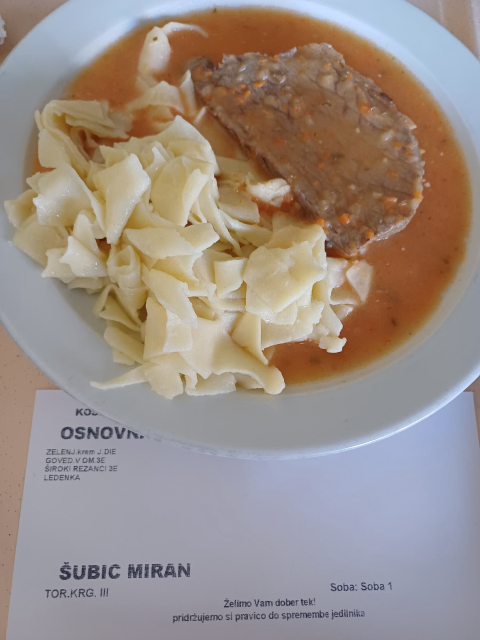

DIAGNOZA:RAK/24/ Štirje hodi, dnevni meni, pet ur .... dnevni meni v sobi 5!

Tole pišem med kemoterapijo v sobi 5

DIAGNOZA:RAK/21/ Dober tek!

Kaj me čaka? Glej simbolično(?) fotografijo...